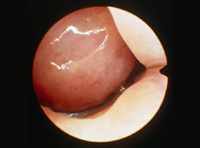

La cirugía endoscópica nasosinusal es una intervención que agrupa variadas técnicas quirúrgicas. Todas ellas tienen en común las actuaciones quirúrgicas en el interior de la nariz, visualizando y manipulando las estructuras a través de las fosas nasales, utilizando instrumentos ópticos (endoscopios con posibilidad de conectarse a sistemas de televisión y grabación de vídeo) e instrumental quirúrgico adecuado.

La cirugía tiene por objetivo la reparación de las estructuras anatómicas anómalas y/o la extirpación de las lesiones que alteran las funciones normales de la nariz, de los senos paranasales y de los demás órganos vecinos, y que son los responsables de causar molestias al paciente. Los síntomas son variados y de diferente intensidad, siendo los principales la dificultad para respirar por la nariz, los dolores en la cara y en la cabeza, la sensación de sequedad nasal o la presencia persistente de mucosidad nasal más o menos espesa, la hemorragia nasal, el lagrimeo persistente, las alteraciones en la visión o en la audición y las alteraciones en el olfato.